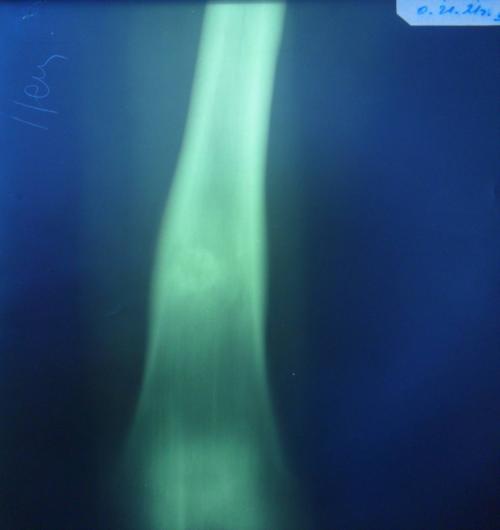

Рентгенологическая картина остеобластокластом длинных трубчатых костей.

Пораженный отрезок кости представляется асимметрично вздутым. Кортикальный слой неравномерно истончен, часто бывает волнистым, может разрушаться на большом протяжении. В месте перерыва кортикальный слой бывает разволокненным или заострен в виде «отточенного карандаша», что имитирует в ряде случаев «периостальный козырек» при остеогенной саркоме. Опухоль, разрушая кортикальный слой, может выходить за пределы кости в виде мягкотканной тени.

Различают ячеисто-трабекулярную и литическую фазы остеобластокластомы. В первом случае определяются очаги деструкции костной ткани, как бы разделенные перегородками. Литическая фаза характеризуется наличием очага сплошной деструкции. Очаг деструкции располагается асимметрично по отношению к центральной оси кости, но увеличиваясь может занимать весь поперечник кости. Характерно четкое ограничение очага деструкции от неповрежденной кости. Костно-мозговой канал отделен от опухоли замыкательной пластинкой.

Из плоских костей чаще всего наблюдаются изменения тазовых костей и лопатки. Нижняя челюсть поражается, примерно в 10% случаев. Характерны также солитарность и изолированность поражения. Определяется вздутие кости, истончение, волнистость или разрушение кортикального слоя и четкое ограничение патологически измененного участка кости. При литической фазе превалирует разрушение кортикального слоя, при ячеисто-трабекулярной фазе - истончение и волнистость последнего.